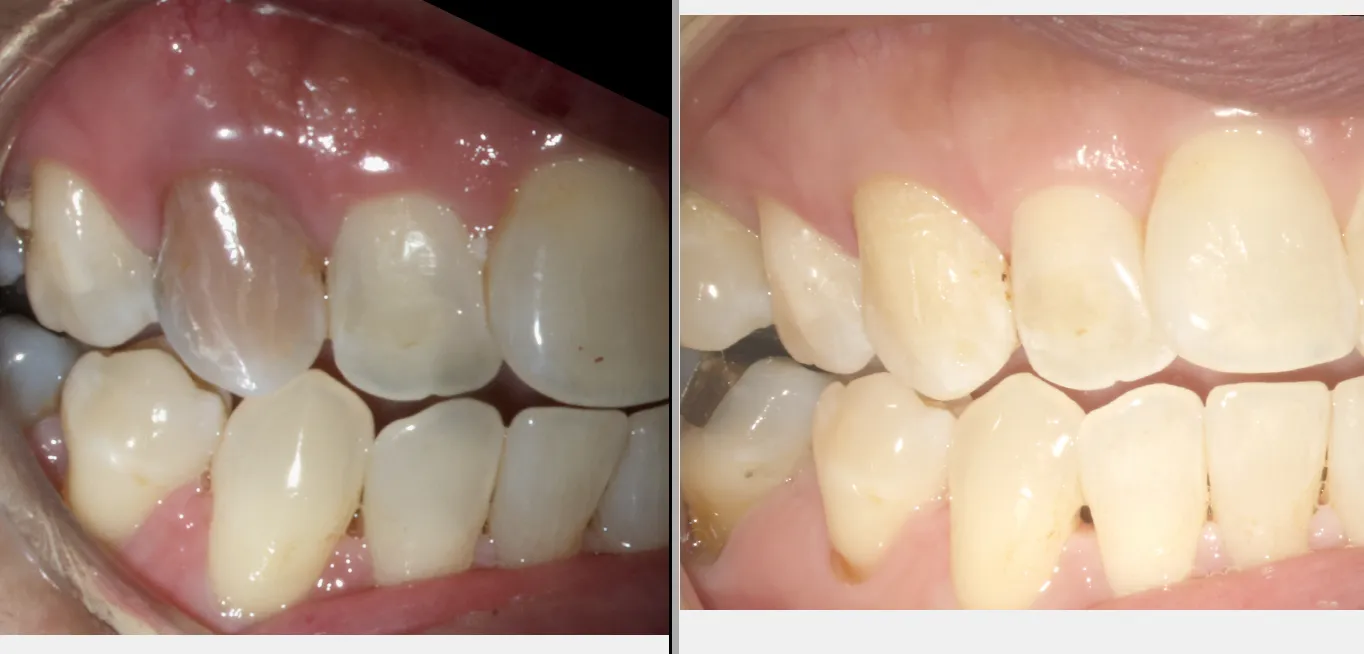

The symptoms of a tooth that needs a root canal can vary, but common signs include the following:

- Pain: This is the most common symptom of a tooth that needs a root canal. The pain can be severe and radiate to other parts of the face, jaw, or neck.

- Sensitivity: Teeth that need a root canal may also be sensitive to hot or cold temperatures.

- Swelling: The gums around the affected tooth may be swollen and tender.

- Tenderness: The affected tooth may also be tender to the touch.